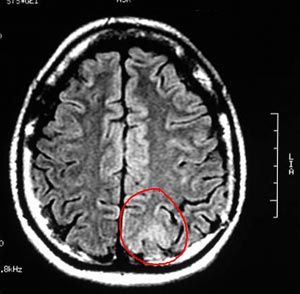

3b) Neurocisticercose

Figura 58 - Ressonância nuclear magnética pré-operatória.